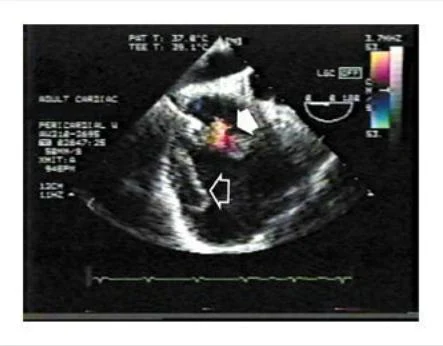

Un ecocardiograma transesofágico que fue llevado a cabo antes del procedimiento, reveló un derrame pericárdico tabicado y lobulado, una masa ecodensa alrededor de la aurícula derecha, con comunicación con la cavidad de la aurícula derecha. El Doppler colo después de la administración de material de contraste reveló una comunicación entre la aurícula derecha y el espacio pericárdico (Figura 2 ). El espacio pericárdico medía 4 cm por 9 cm y el defecto en la aurícula derecha medía 5 mm . La realización de una ventana pericárdica fue abortada.

Figura 2. Eco Doppler Color Obtenido Durante el Ecocardiograma Transesofágico.

La imagen muestra flujo a través de una comunicación entre la aurícula derecha (flecha sólida) y el espacio pericárdico, donde la masa puede ser vista (flecha abierta).